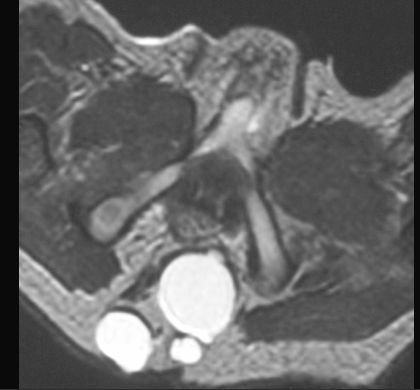

POTWORNIAK

MR